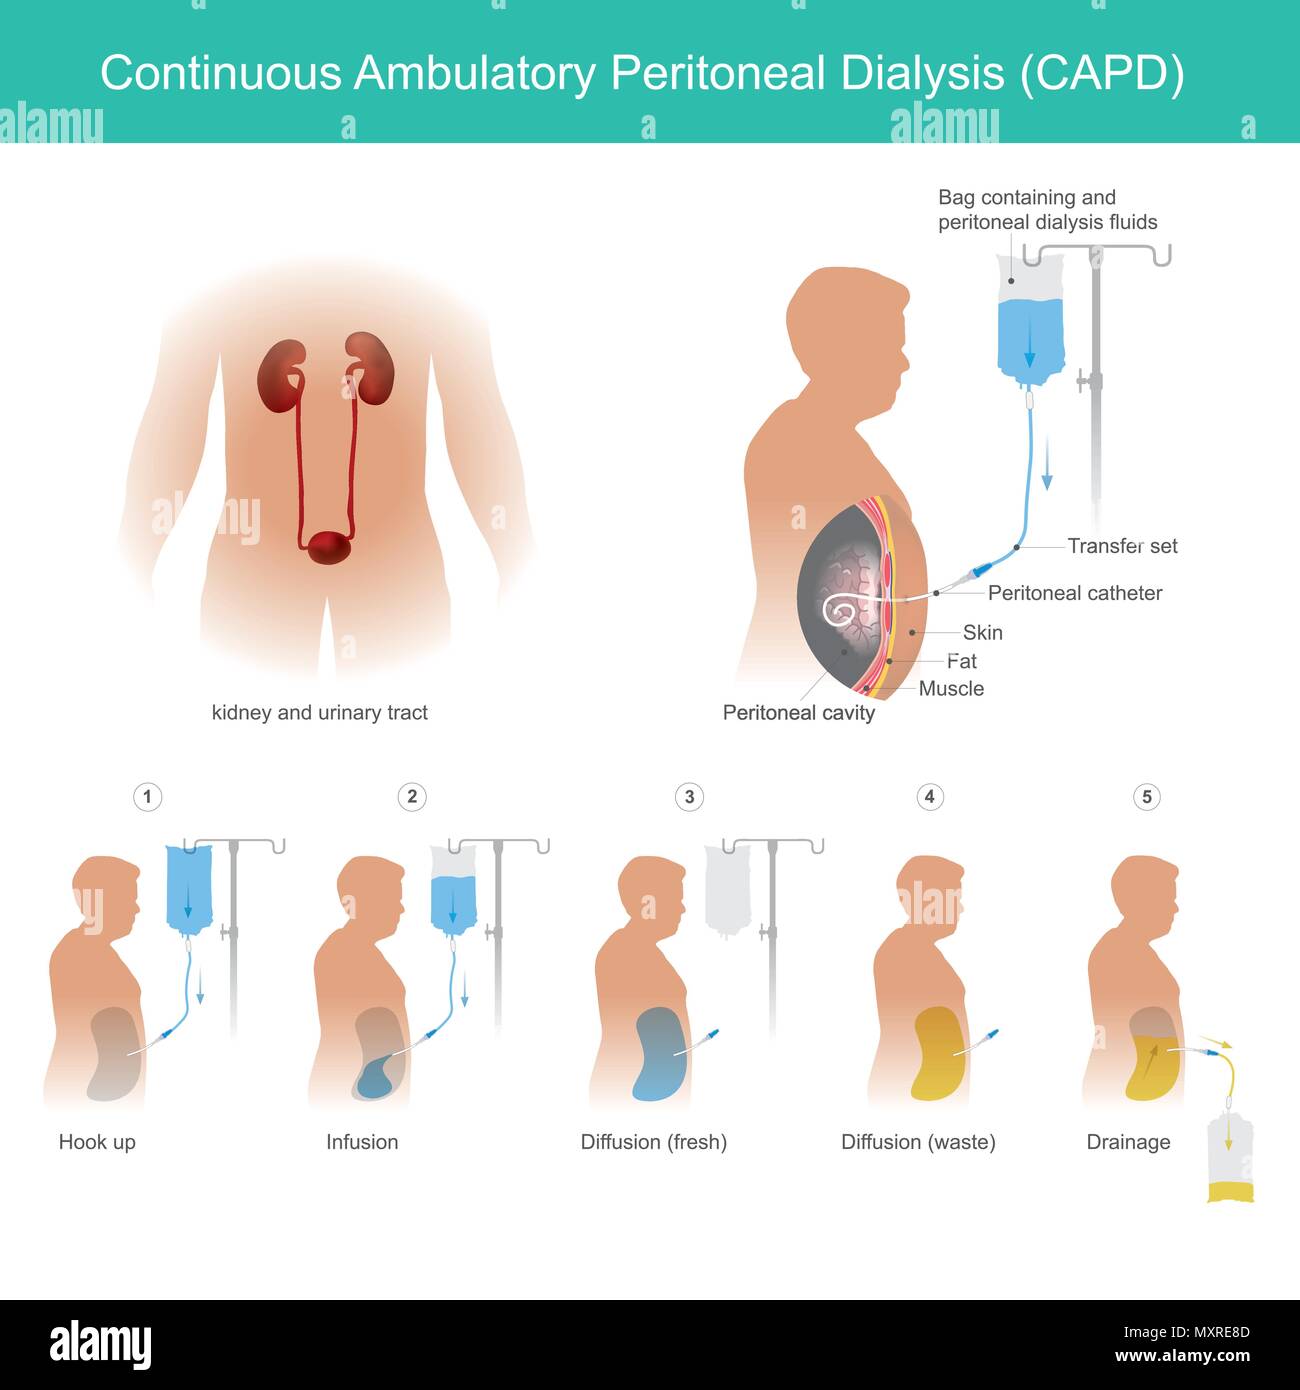

Si tratta di impieghi tecnici cavità peritoneale per il trasporto del fluido di dialisi per la permeabilità di capillari di sangue in una cavità peritoneale. Illustrazione Vettorialehttps://www.alamy.it/image-license-details/?v=1https://www.alamy.it/si-tratta-di-impieghi-tecnici-cavita-peritoneale-per-il-trasporto-del-fluido-di-dialisi-per-la-permeabilita-di-capillari-di-sangue-in-una-cavita-peritoneale-image188600845.html

Si tratta di impieghi tecnici cavità peritoneale per il trasporto del fluido di dialisi per la permeabilità di capillari di sangue in una cavità peritoneale. Illustrazione Vettorialehttps://www.alamy.it/image-license-details/?v=1https://www.alamy.it/si-tratta-di-impieghi-tecnici-cavita-peritoneale-per-il-trasporto-del-fluido-di-dialisi-per-la-permeabilita-di-capillari-di-sangue-in-una-cavita-peritoneale-image188600845.htmlRFMXRE8D–Si tratta di impieghi tecnici cavità peritoneale per il trasporto del fluido di dialisi per la permeabilità di capillari di sangue in una cavità peritoneale.